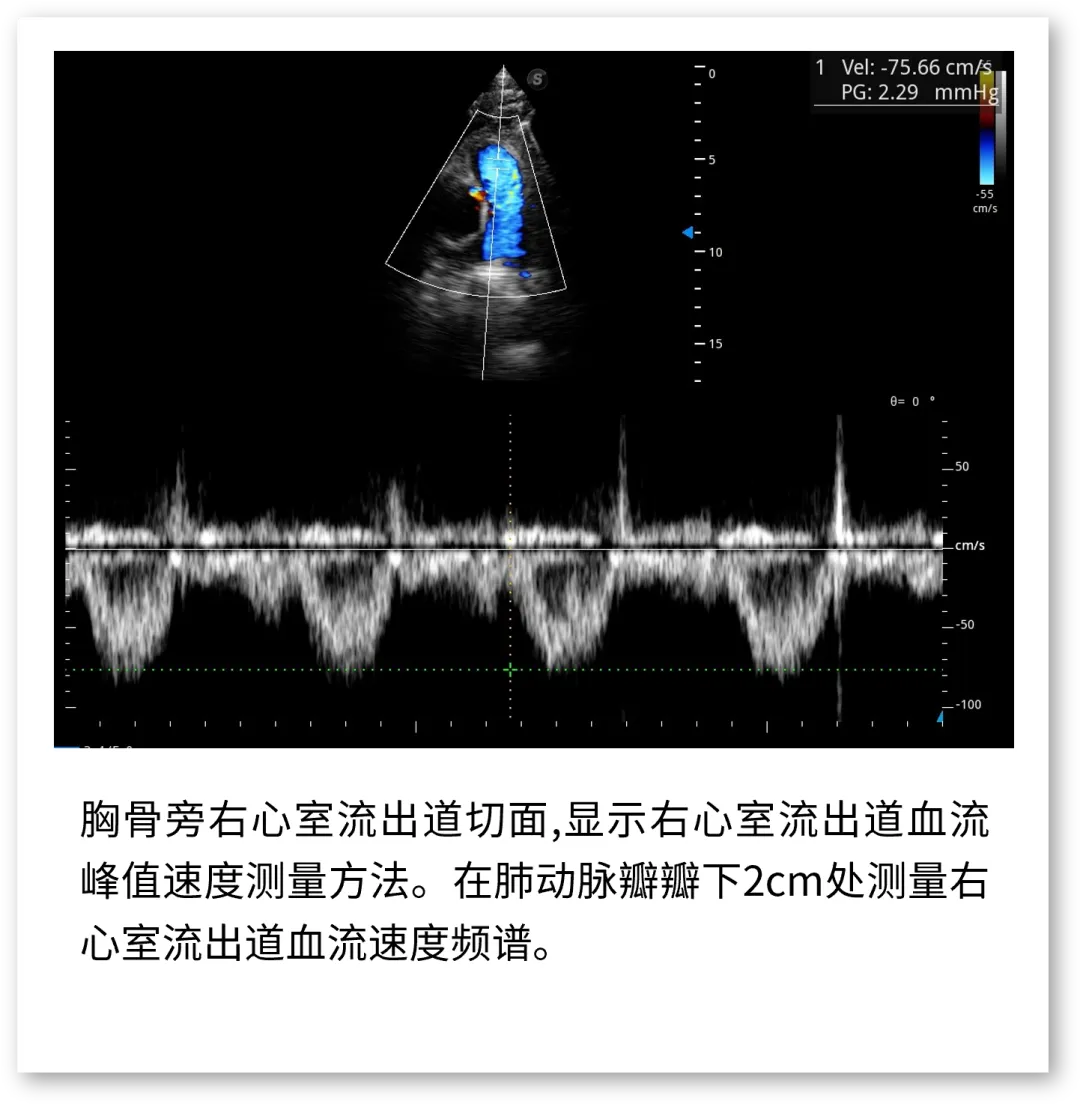

开立医疗联合武汉大学中南医院心血管病医院,将《心脏超声检查规范化中国专家共识 (2024版)》内容与实际临床工作需求融合,精心制作了指南挂图,助力标准采集,规范测量,期待这份实用且高清的工具,能成科室提升超声质效的助手!